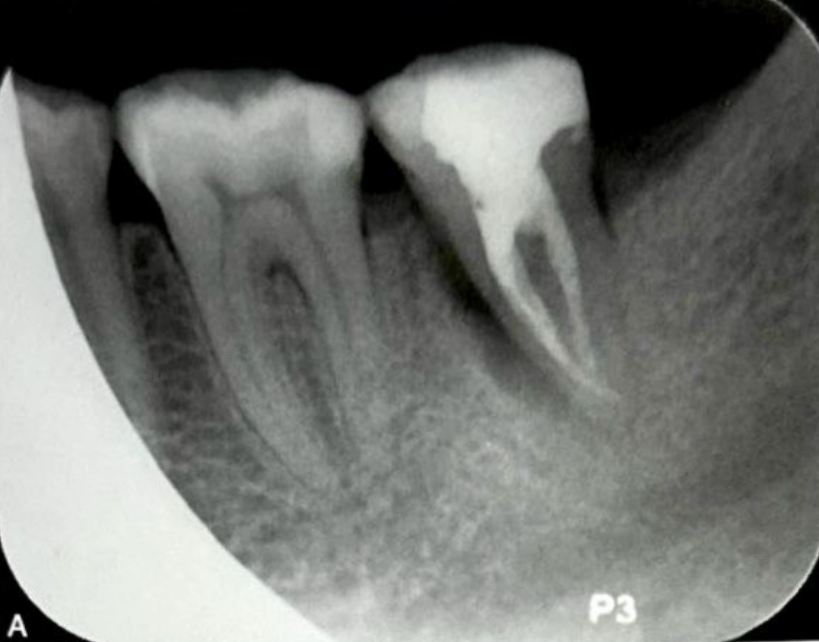

导致根旁牙槽骨破坏的可能病因有根裂、侧支根管、根折、根旁囊肿、牙骨质撕裂等。当根管侧支位于牙根中段时,感染破坏根周牙槽骨,可形成类似根裂的影像学特点,如图3所示,A为口内像颊侧面观,示左下颌第一磨牙近中近龈缘处牙龈窦道(箭头);B为根尖片示根管充填良好,近中根根尖以及根周大范围透射影,波及根分叉区;C为CBCT矢状位;D为CBCT冠状位;E为CBCT水平位,近中根根尖、根周以及根分叉区骨质破坏;F为左下颌第一牙行显微根尖外科手术,切开翻瓣牵拉 ;G为根尖周刮治和根尖切除;H为探查,近中根未见根裂线,近中面中段见根管侧支(箭头);I为主根管和根管侧支逆行预备和充填;J为术后根尖片,可见根管侧支(箭头);K为术后2个月随访根尖片;L为术后4个月随访根尖片;M为术后7个月随访根尖片;N为术后24个月随访根尖片,根周和根尖周完全愈合。